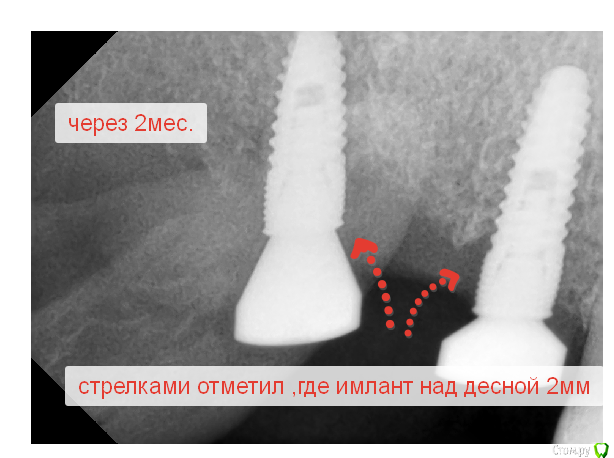

Sergiosse Опубликовано 21 декабря, 2016 Поделиться Опубликовано 21 декабря, 2016 Меньше 2 месяцев назад были установлены два импланта диаметром 4,2х12и10 в области 16 17 зубов одномоментно с удалением. Скриншоты выкладывал в теме: оголился имплант. Сейчас посоветовавшись с вами Уважаемые форумчане пришел к выводу о необходимости переустановить имплантанты . С какими особенностями могу столкнуться. Кто делал подобные манипуляции, пожалуйста подскажите. Заранее спасибо всем ответившим.Р.С. Недавно один уважаем доктор сказал, что, я не настоящий имплантолог. Стану им только тогда, когда удалю собственноручно установленный имплант. Чувствую скоро, я стану настоящим Ссылка на комментарий